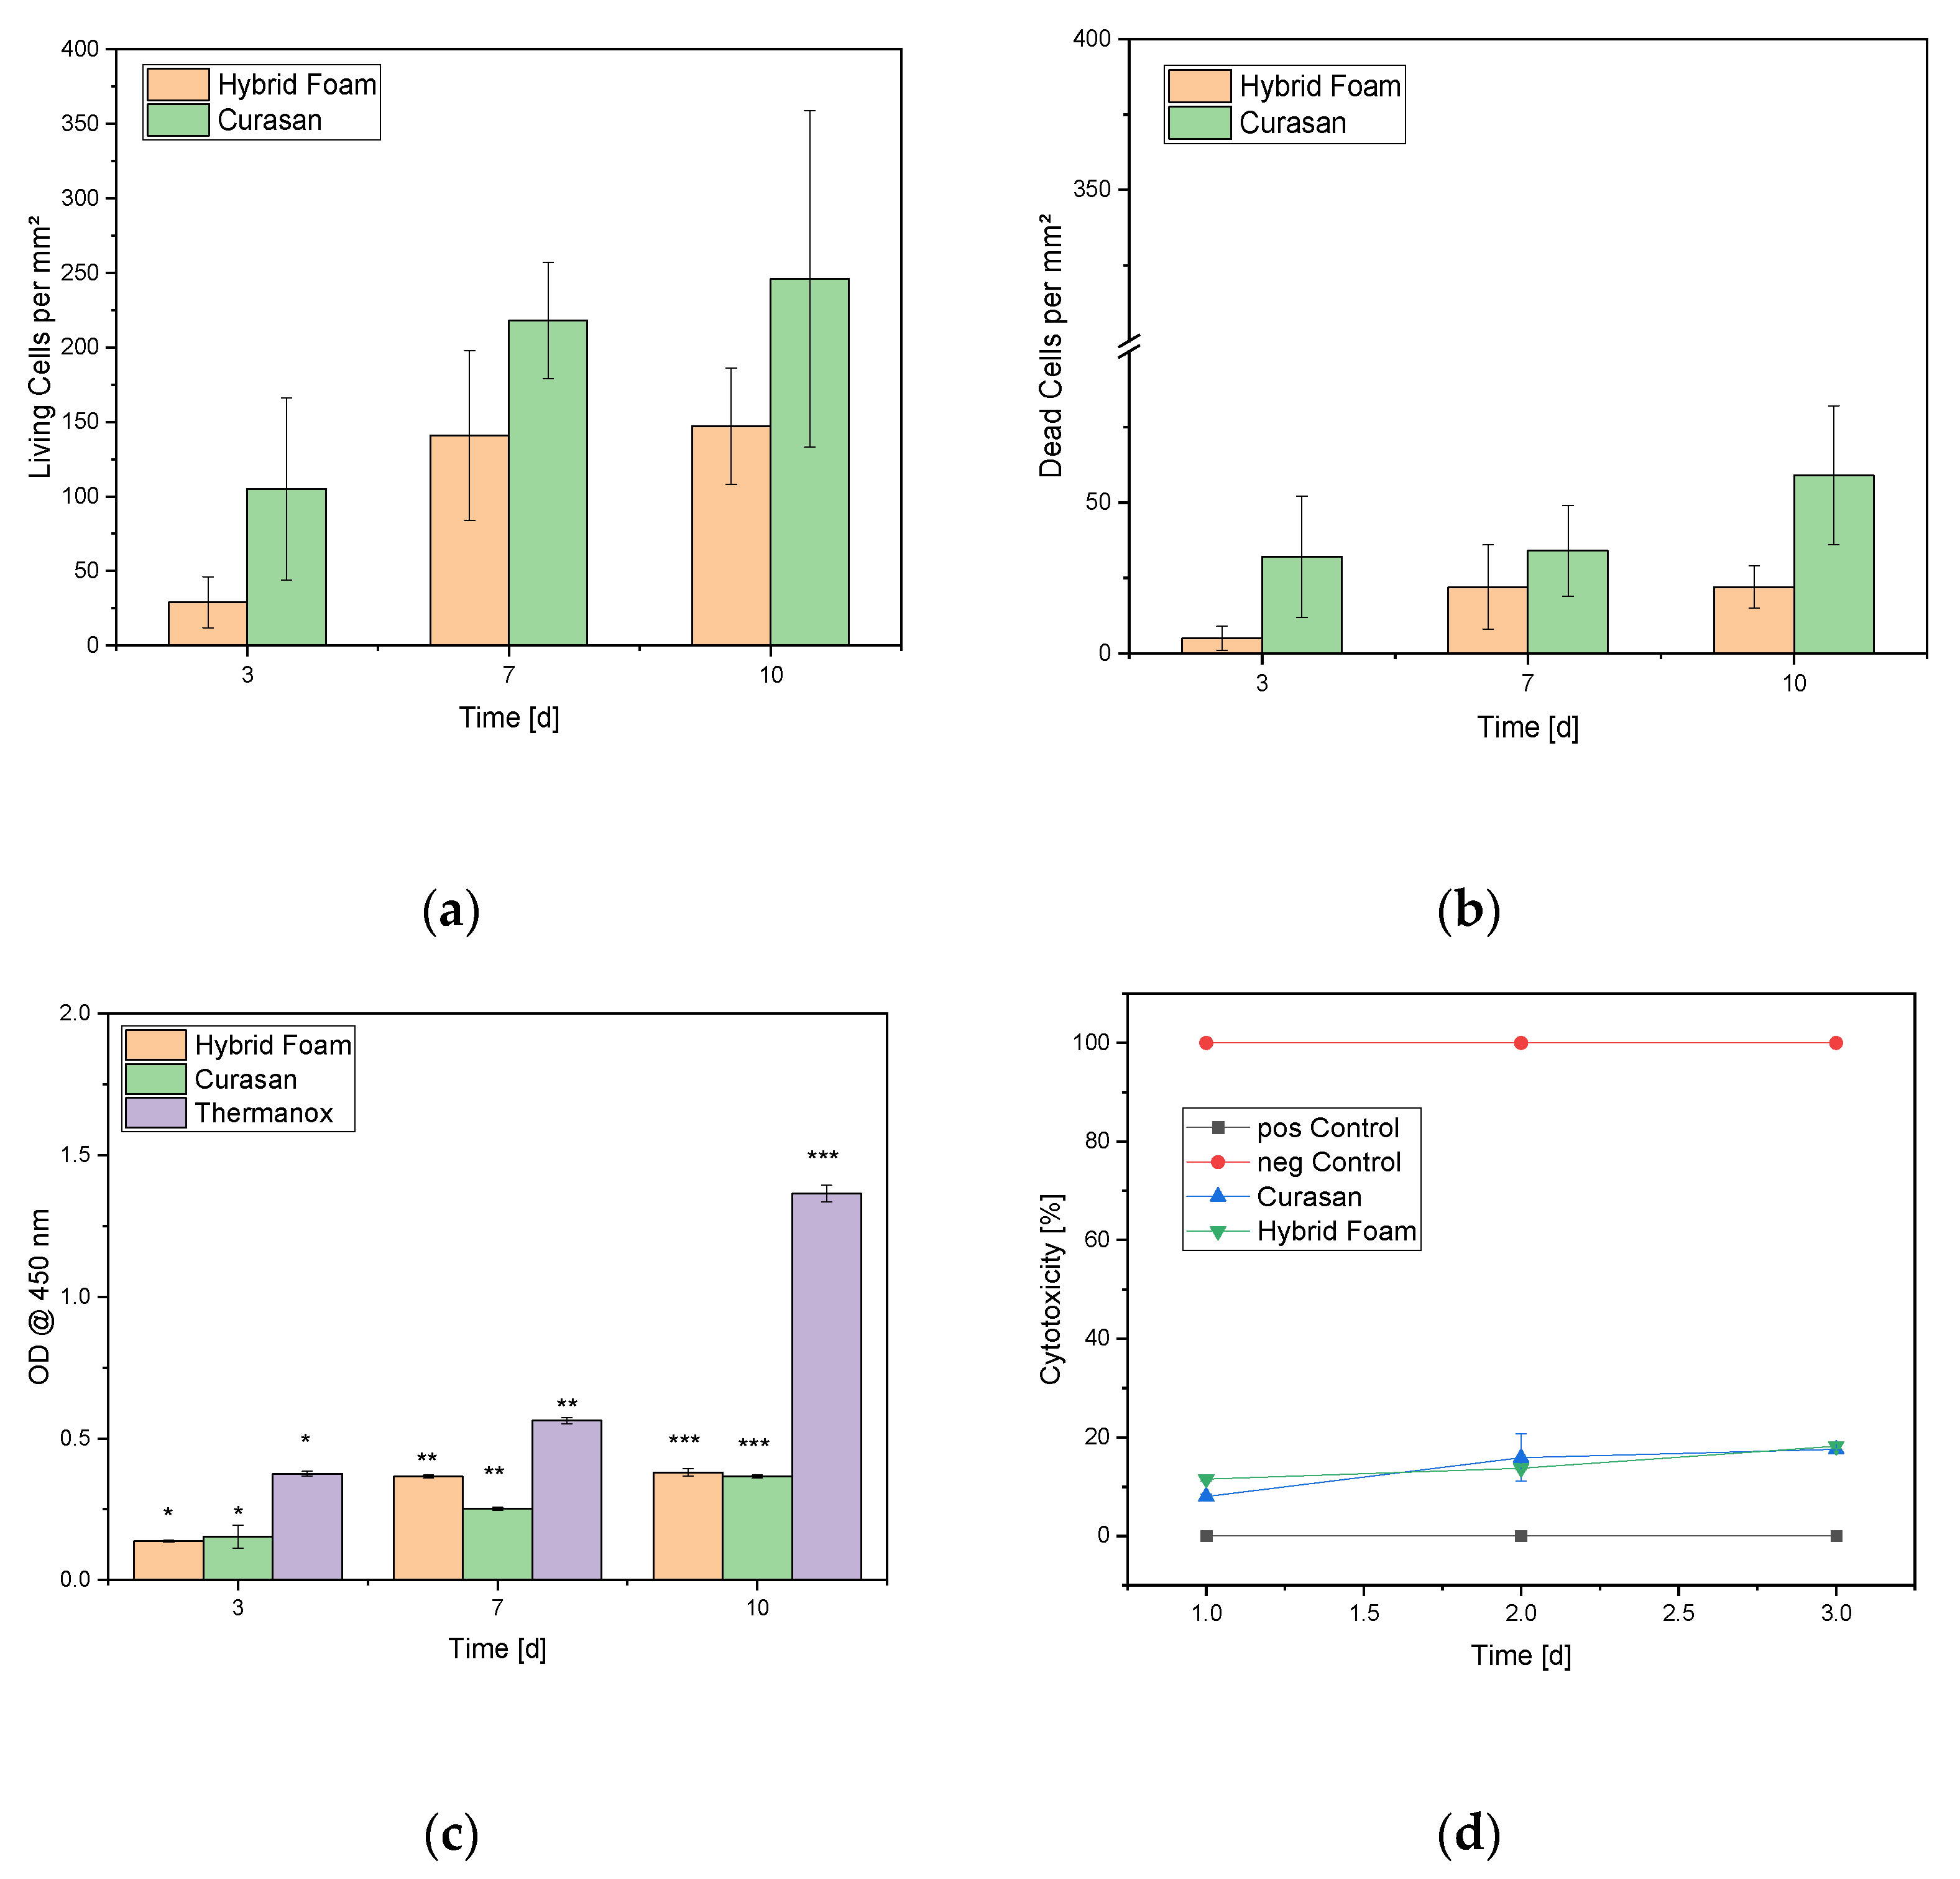

3.3. In Vitro Biocompatibility

3.3.1. Live/Dead Assay

3.3.2. Cell Proliferation Assay

3.3.3. LDH Assay

3.3.4. GIEMSA Staining

4.2. Biocompatibility

5. Conclusions